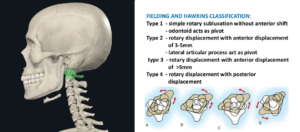

最近の研究では、メニエール病症状の背景に頭蓋頸椎角度異常が潜んでいる可能性が報告されています。

前庭神経炎とは、突然激しいめまいを感じ、吐き気、むかつき、嘔気を伴い、バランスを取ることが困難になる疾患です。前庭神経の炎症により発生すると知られていますが、原因が明確に解明されているわけではありません。対症的な薬物治療で回復を期待しますが、めまいや随伴症状が完全に消失せず、持続的に現れる場合が多いのです。